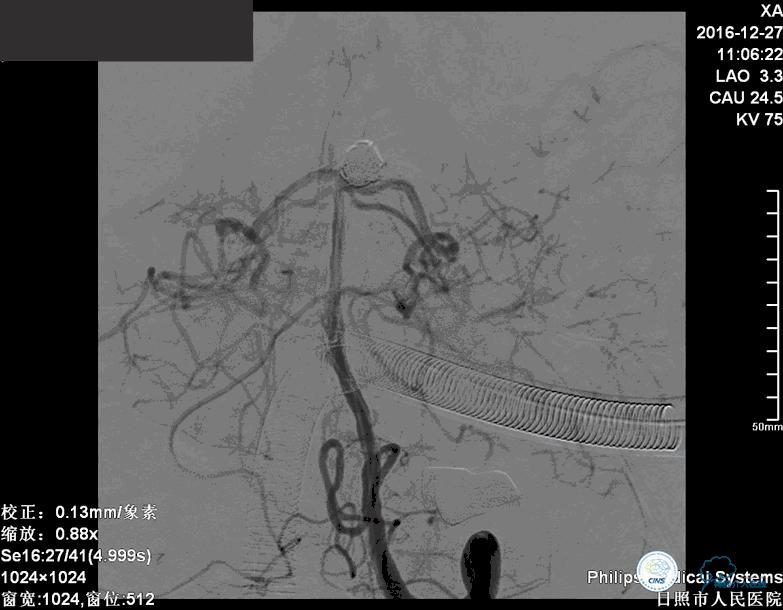

确诊:基底动脉顶端宽颈未破裂动脉瘤,动脉瘤大小约6mm×9mm,瘤颈约4毫米。

注:以下为动图

分别选择了7mmx30cm、6mmx30cm、2个4mmx15cm、3mmx8cm、2mmx8mm Target共6个弹簧圈进行栓塞。

这个病例我们采取了双微导管技术弹簧圈栓塞治疗。

我们将两个微导管分别送入动脉瘤腔内,其中一个塑为u型,一个直头。两个微导管,一个位于动脉瘤较深的部位,1个位相对较浅的部位,交替进行栓塞。

前两个弹簧圈对动脉瘤的瘤颈和动脉瘤的后部进行了栓塞。成篮稳定以后,开始对动脉瘤的内部和前部进行栓塞。